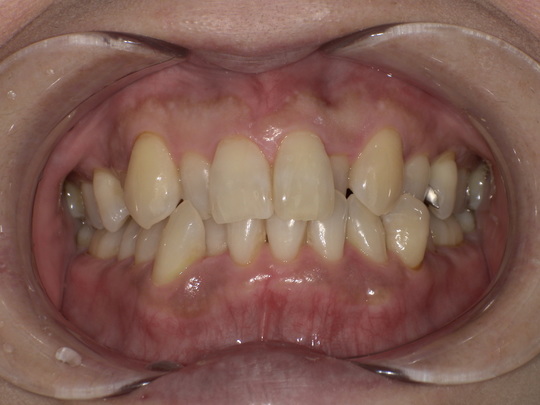

ステイン除去

BEFORE

AFTER

年齢:60代女性

治療内容:エアーフローによる歯の着色汚れ、ステイン除去

治療期間/通院回数:1回

費用: ステインコース 8,800円